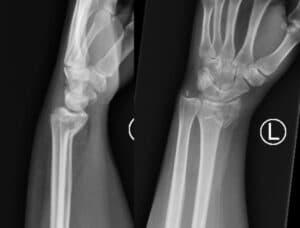

Barton – involves dorsal or volar intraarticular surface, often with radiocarpal dislocation/subluxation.

Chauffeur (aka Hutchinson fracture) – intraarticular fracture of the radial styloid process.